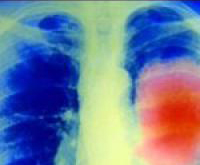

Рак легких развивается бессимптомно и обнаруживается на поздних стадиях. Но биоинженеры и ученые-медики из Университета Миссури создали технологию для ранней диагностики болезни.

Рак легких на ранних стадиях не вызывает симптомов, пока он не прогрессирует. Когда это происходит, человек может испытывать дисфагию во время еды...